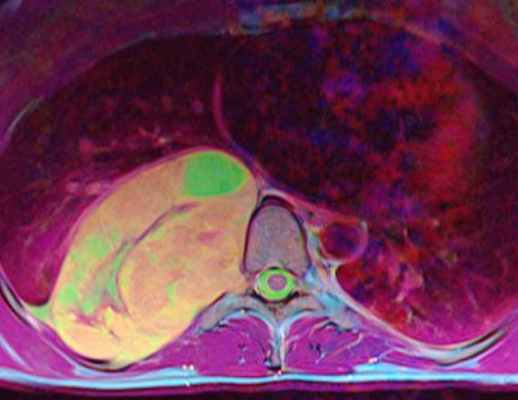

(Слева) Схема аксиального среза: дольчатые плексиформные нейрофибромы, характерные для НФ1. Видны признаки эрозии опухолью левого корня дуги.

(Справа) Аксиальный срез, Т2-ВИ: объемное образование в просвете правого межпозвонкового отверстия с увеличением объема отверстия и вдавлением тела шейного позвонка. Интраспинальный экстрадуральный компонент опухоли стал причиной выраженного стеноза спинномозгового канала. Опухоль характеризуется преимущественно гиперинтенсивным сигналом с неравномерной гипоинтенсивностью в центральной части. (Слева) На фронтальном Т1-ВИ с КУ визуализируется накапливающее контраст паравертебральное объемное образование на уровне L1-L2 слева, распространяющееся в левое невральное отверстие и минимально оттесняющее дуральный мешок. Ремоделирование костных структур привело к расширению неврального отверстия L1-L2 и истончению корня дуги L1.

(Справа) Аксиальный срез, Т2-ВИ, этот же пациент: зоны гипоинтенсивного Т2-сигнала в центральной зоне опухоли с гиперинтенсивным сигналом по периферии. Это симптом мишени, являющийся неспецифическим признаком, однако встречающийся чаще при нейрофибромах, чем при шванномах.

МРТ позвоночника. Аксиальная Т2-взвешенная МРТ грудного отдела. Невринома по типу “песочных часов”. Цветовая обработка изображения.